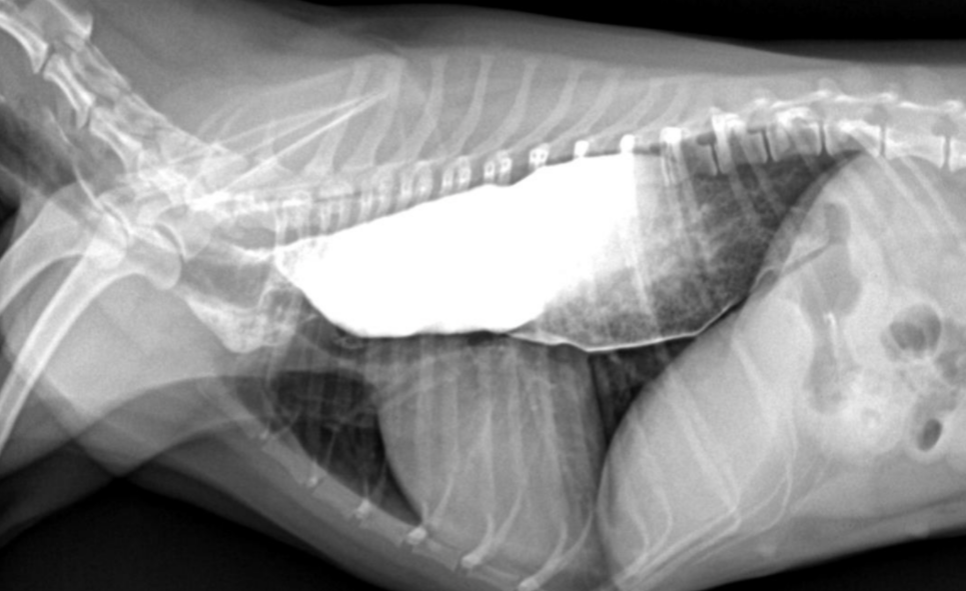

์ํ์ฅ : GD vs. GDV

- ๊ฐ๋ณ์ key point๋ pylorus์ ์์น & ์์ ๋ถํํ(compartmentalization) !

- ์ ์์ ์ธ ์์น๋ ์ธ์ธก์์์ ์๋์ชฝ, ๋ณต๋ฐฐ์์์ ์ผ์ชฝ์ ์์น.

- GD๋ ์๊ฐ ํ์ฅ๋์ด ์์ผ๋, ์์น๋ ๊ทธ๋๋ก.

- GDV๋ ์ฅ์ด ๊ผฌ์ด๋ฉด์ ์์น๊ฐ ๋ฌ๋ผ์ง๋ฏ๋ก, pylorus์ ์์น๊ฐ ์ธ์ธก์์์ ์์ชฝ

| GD | GDV | |

|---|---|---|

| VD | - greater curvature ์ผ์ชฝ(์ ์) * 360๋ ํ์ ์์๋ ์ผ์ชฝ์ ์์น | - greater curvature ์ค๋ฅธ์ชฝ (180๋ ์ผ์ ) - duodenum ์์น๋ ํจ๊ป ๊ผฌ์ |

| RL | - pylorus๊ฐ ์๋์ชฝ(์ ์) | - pylorus ์์ชฝ - ์์ ๋ถํํ(compartmentalization) : ๋ถ๋ฐฉ ํ์ธ - gastric band (soft tissue) ๊ด์ฐฐ |